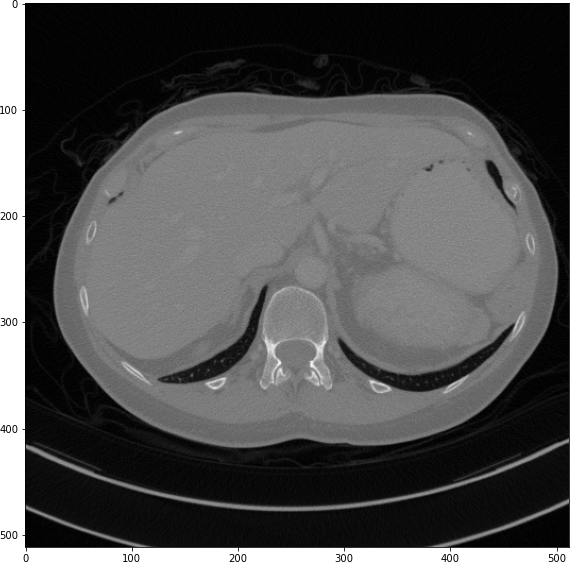

The results from all conducted experiments, represented as mean ±plus-or-minus\pm standard deviation, are tabulated in this section. We assessed the performance of our proposed simulation method against Simple Averaging, Gaussian Averaging, and Direct Downsampling. This was accomplished by simulating images with a thickness of 3mm from those with a thickness of 1mm, utilizing the 2016 Low Dose CT Grand Challenge dataset. The results outlined in Table III provide a comparative analysis of different thick-slice simulation methods used in two datasets from the 2016 Low Dose CT Grand Challenge. Both the PSNR and the RMSE were used as key performance indicators for these methods. The data clearly demonstrate that the proposed method significantly outperformed Simple Averaging, Gaussian Averaging, and Direct Downsampling in both datasets (D45 and B30). The highest PSNR values were obtained with the proposed method, yielding 49.7369 ±plus-or-minus\pm 2.5223 and 48.5801 ±plus-or-minus\pm 7.3271 for D45 and B30 datasets, respectively. The proposed method also registered the lowest RMSE with values of 0.0068 ±plus-or-minus\pm 0.0020 and 0.0108 ±plus-or-minus\pm 0.0099 for D45 and B30, respectively. These results indicate a superior level of accuracy and reliability in the proposed method. The statistically significant differences were confirmed by a Wilcoxon signed-rank test with p-value ¡ 0.05, implying that the improvements from the proposed method were not due to random chance. These findings support our first hypothesis that the proposed simulation method provides a more efficient and precise approach to thick-slice simulations compared to traditional methods. To provide a more comprehensive evaluation, visual comparisons from axial, coronal and sagittal plane were also undertaken, as depicted in Figures 2 to 4. In summary, Our proposed method demonstrated substantial enhancements in terms of both PSNR and RMSE, indicating a distribution more closely aligned with the authentic thick-slice image.

Refer to caption

(a) True Thick-slice image

(b) Simple Averaging

RMSE: 0.0250, PSNR: 38.0530

(c) Gaussian Averaging

RMSE: 0.1758, PSNR: 21.1182

(d) Direct Downsampling

RMSE: 0.0348, PSNR: 35.1697

(e) Proposed Simulation

RMSE: 0.0051, PSNR: 51.8504

Figure 3: Coronal-plane thick-slice image quality comparison across four simulation methods.